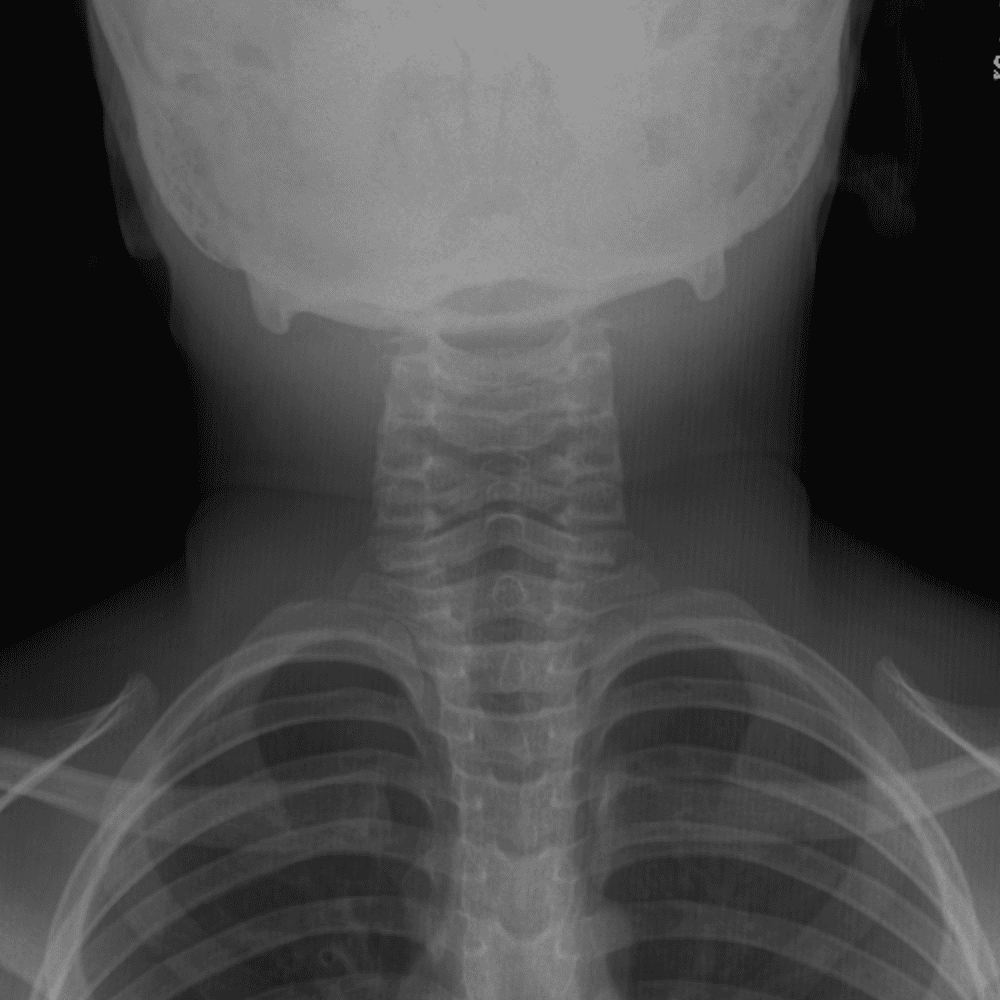

Peds Chest

Practice

Simulates call by including subtle or difficult cases and some normals.

50 cases